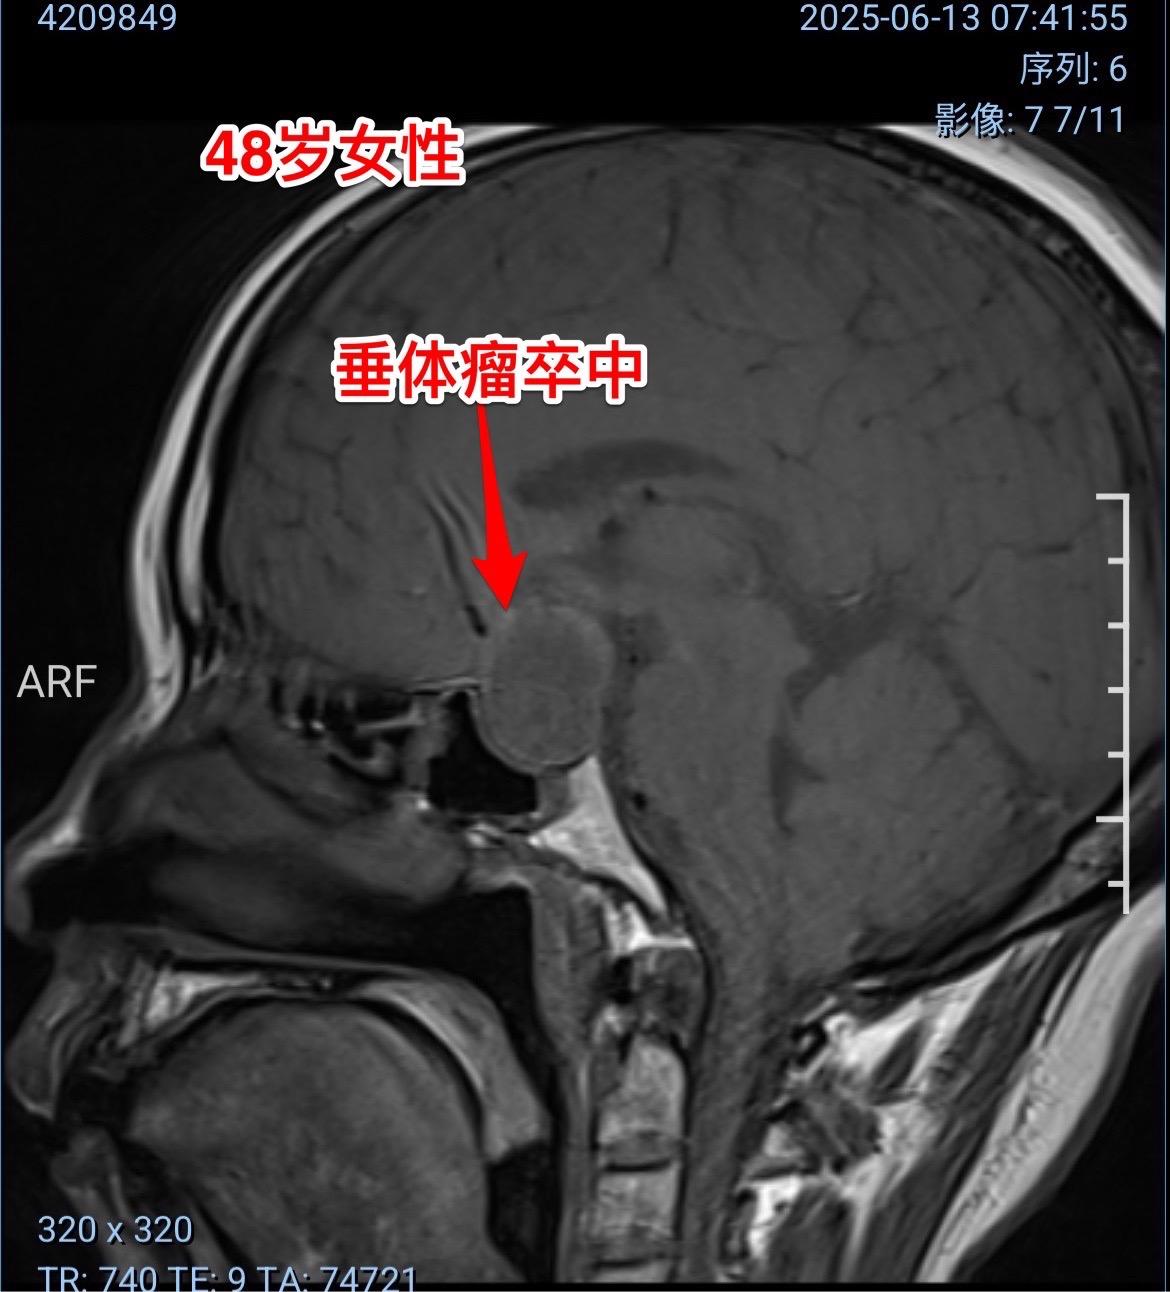

垂体瘤卒中,女教师6月12日突发视力下降。48岁定州市女教师6月12日早晨起床时尚无不适,上午出现眼前发花、白一块黑一块,随后双眼视力下降,几乎失明。 到当地医院行头部CT检查发现鞍区出血了,怀疑是动脉瘤破裂,随后作了磁共振、MRA检查,排除了动脉瘤破裂,诊断为垂体瘤卒中。 6月13日上午患者一家人自驾车出发,中午到了三博脑科医院。下午急诊行经鼻手术切除垂体瘤。 时间紧迫,极力挽救视力。 6月14日早晨患者自述视力有好转。